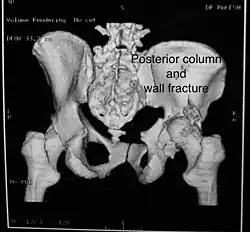

Posterior column and wall fracture as seen on 3D CT